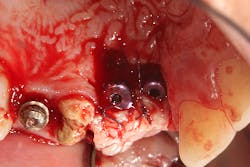

The patient was referred to a periodontist who first augmented the edentulous site with a hard-tissue graft and membrane (figures 8 and 8a). Six months later, implants were placed in ideal positon (figure 9).

At the time of Stage II, six months after implant placement, a palatal roll soft-tissue augmentation was performed (figures 10 and 10a). Six weeks later, the area was provisionalized with new temporaries to develop soft tissue.